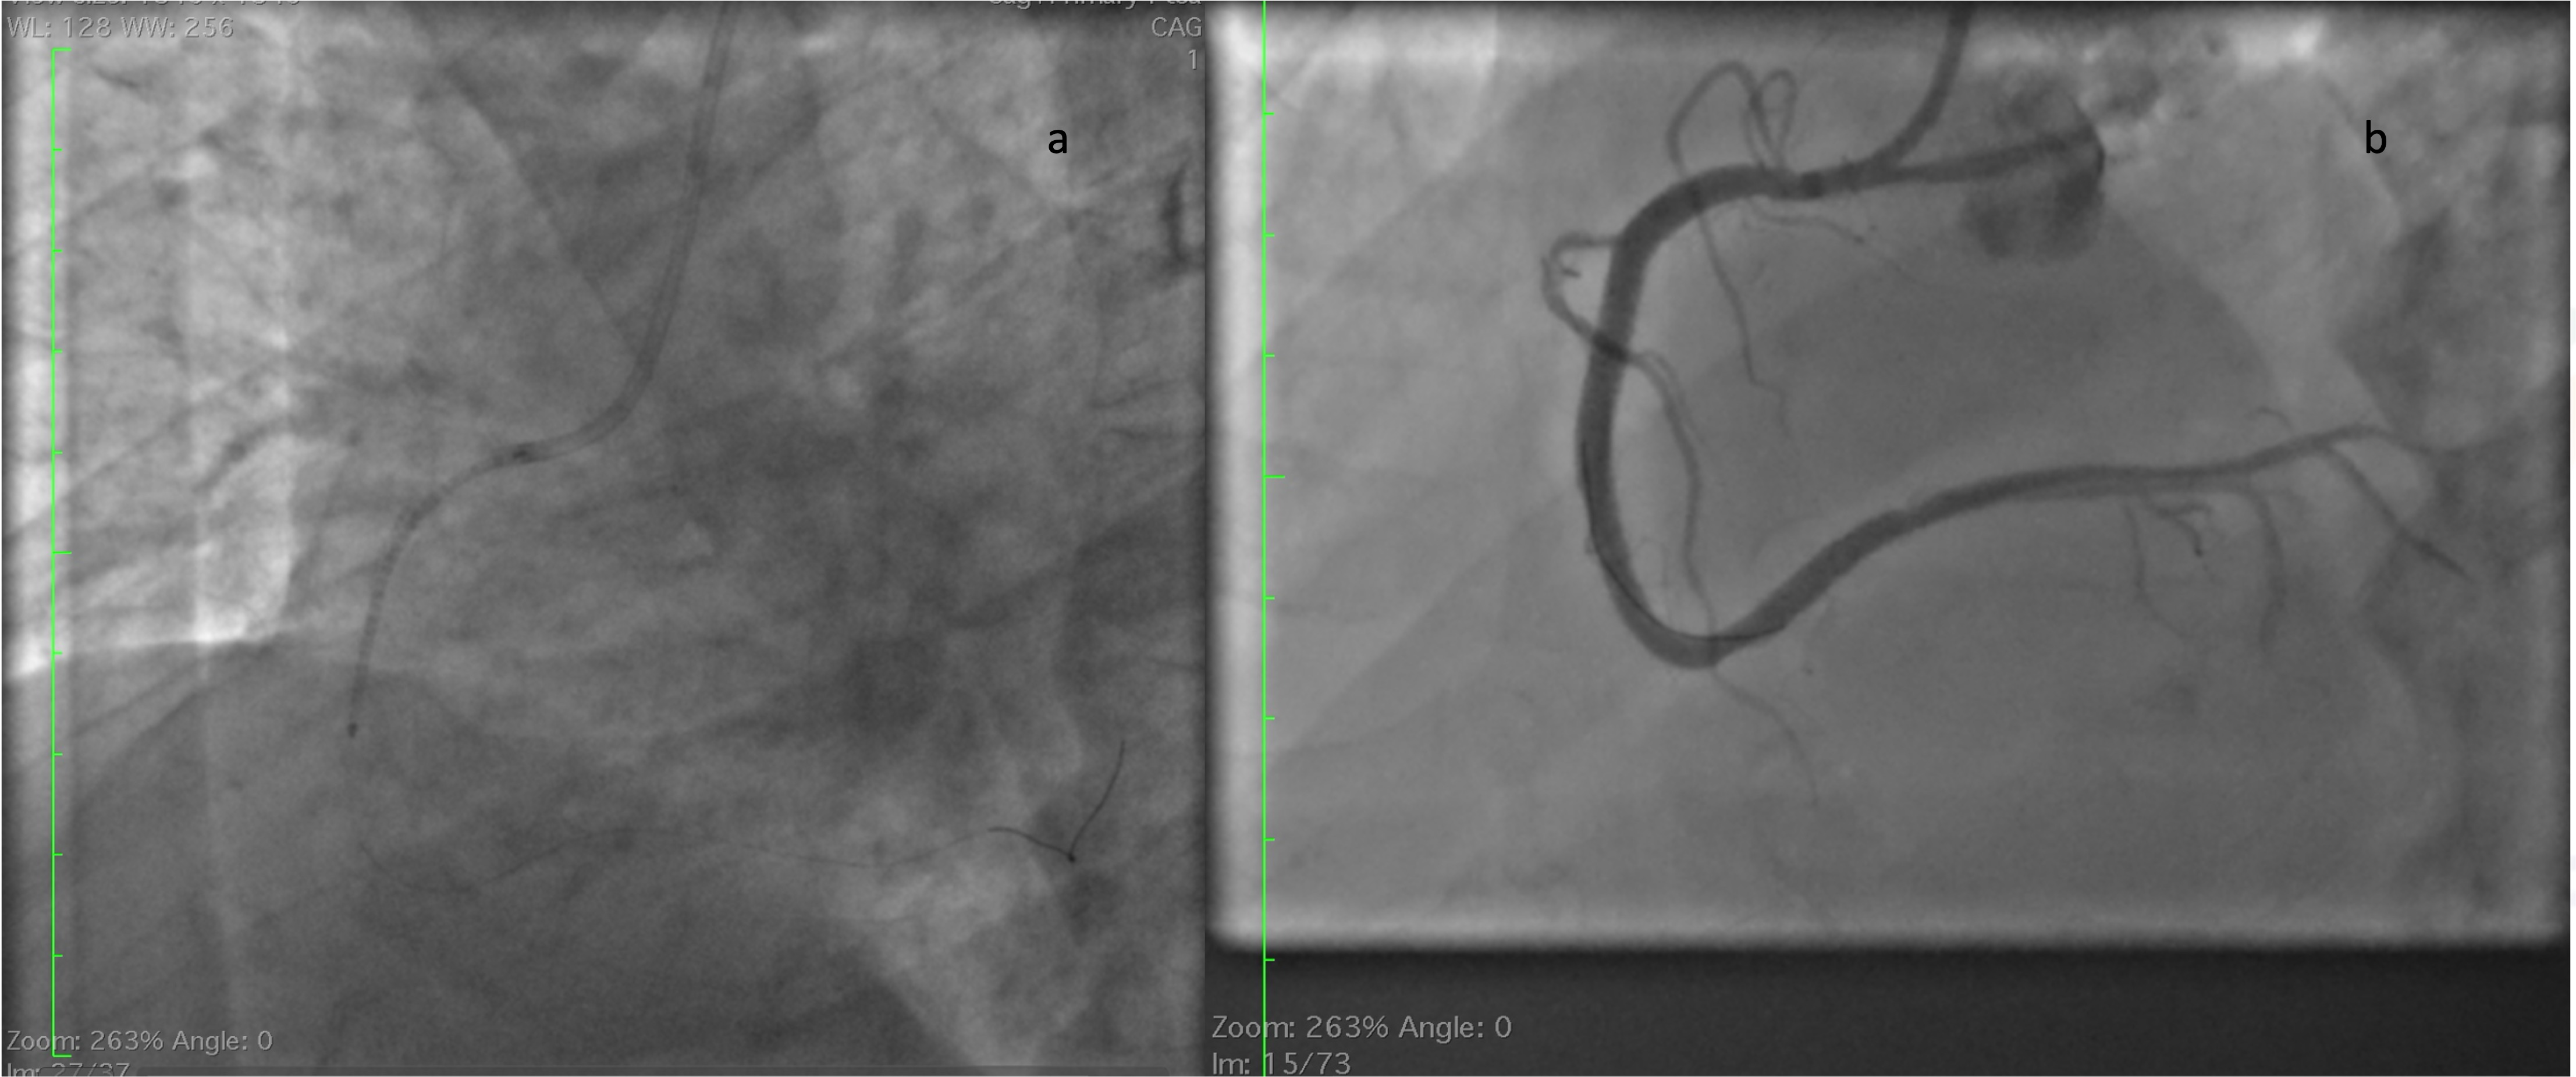

Immediately a 6 French JR 3.5 catheter was taken and right coronary artery ostium was engaged. Then a work horse wire was parked distally in posterolateral vein branch. Then a 2.75 x 23 mm Drug eluting stent was deployed across the lesion (Figure 4a). After deployment angiogram showed haziness at the distal edge of the stent. Nitroglycerine, nicorandil and tirofiban injections were given and check angiogram showed no improvement in the distal edge haziness (figure 4b). In view of possible dissection it was decided to cover the distal edge with one more DES. While passing the second DES due to poor catheter support manipulation led to degloving of the stent from balloon (figure 5a). As the wire was still in position we tried to pass the same stent balloon through the degloved stent and tried to remove en masse. However balloon. Couldn¡¯t be passed through the stent (Figure 5b). We then tried a 1 x 8 mm balloon to pass through the stent and inflated the balloon beyond the stent and tried to pull the stent into guide. However the stent could be negotiated till the guide tip but couldn¡¯t enter the guide (Figure 5c). As further manipulations may risk the stent being lost in systemic circulation with risk of embolization, we have decided to crush the stent with another stent. So a 3 x 33 mm DES was positioned over a newly placed wire and deployed crushing the previously degloved stent. Check angiogram showed good flow with no visible dissections at the proximal stent. (Figure 6)